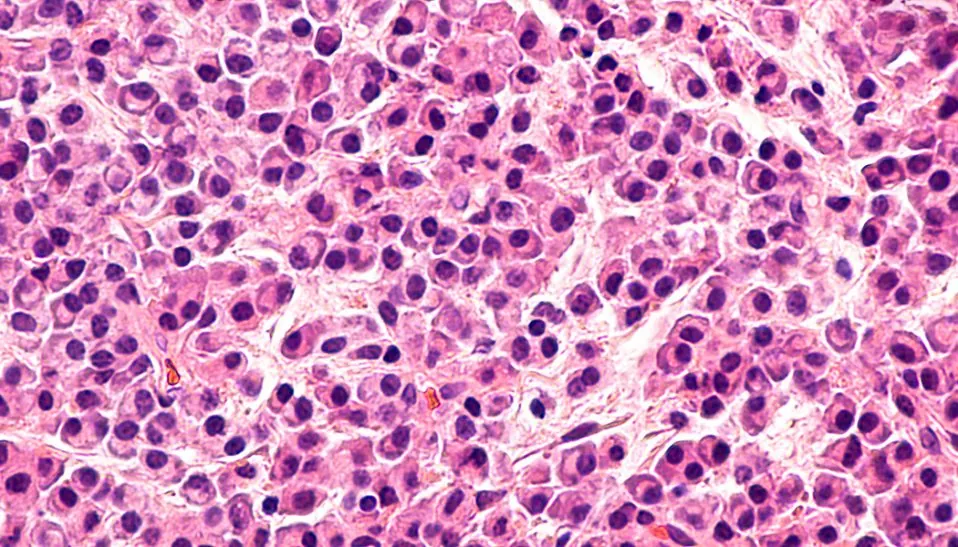

New Therapeutic Option for Triple-Negative Breast Cancer

Triple-negative breast cancer, one of the deadliest and most aggressive forms of breast cancer, spreads quickly, is resistant to many chemotherapies and is likely to reoccur even after a seemingly successful round of therapies. The cause for the later is the resiliency of a subset of cancer cells called cancer…...